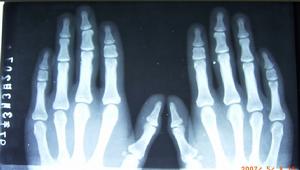

所謂的腳趾短小,其實並非如此,患者的腳趾並不短,真正短小的是腳趾後面的一段骨頭,醫學上專業詞叫跖骨,所以這種病的專業術語叫做:先天性第四跖骨短小症。患者出生時足趾正常,一般在7,8歲時,第四跖骨的骨骺過早閉合,停止生長,而其他腳趾正常發育,這樣到成年後,形成了第四足趾短小畸形。許多患者說跟穿鞋擠壓有關、也有人說外傷所致,其實這些都不是根本原因,遺傳是我們能看到到主要病因,儘管這個致病的基因一直沒有被成功克隆,老外文獻也說和遺傳關係不大,但我們在臨床上看到的母女兩代畸形的非常普遍。一般女多於男,單側多於雙側,左右似乎差別不大。不僅第四跖骨容易受累,其他的單一跖骨短小,也不少見,如第一跖骨短小症等,但第四跖骨短小者居多。致病機理

短指(趾) 短指(趾) 骨硬化3、行走不便,人在行走時,當人的體重前移至前腳掌時,力量有第5趾傳至第4趾,以此類推至第1趾。第4趾的短小破壞了這一關係,使第5趾和第3趾承受了過多重力,有可能導致這一區域酸痛或其他不適。同時由於第四趾不承重,第四趾會上翹,常會摩破襪子和鞋子。不過第四趾短小的病人,一般從功能上講,對足的影響比較小,主要還是外觀不雅,使女孩蒙受更多的心理陰影。